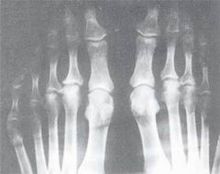

關節炎風濕病指主要侵犯關節、肌肉、骨骼及關節周圍的軟組織,如肌腱、韌帶、滑囊、筋膜等部位的疾病。在現代醫學概念中風濕病是風濕性疾病的簡稱,泛指影響骨、肌肉及其周圍軟組織,如滑囊、肌腱、筋膜、血管、神經等一大組疾病。風濕性疾病包含瀰漫性結締組織病(如系統性紅斑狼瘡、乾燥綜合症、炎性肌病、硬皮病、混合性結締組織病、白塞病等)、系統性血管炎、脊柱關節病(如強直性脊柱炎、反應性關節炎、瑞特綜合症等)、骨關節炎、骨質疏鬆症等上百種以上的以累及骨、關節等結締組織為主的疾病總稱。